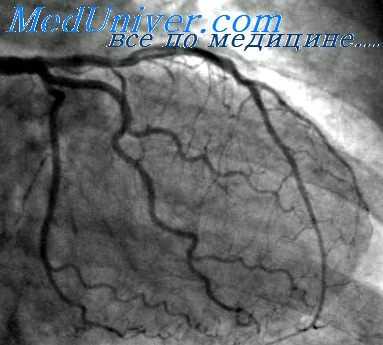

Присоединение атомов йода к молекулам органических веществ позволило создать новые, менее токсичные рентгеноконтрастные вещества. В 1925 – 1929 гг. компанией Эрнеста Шеринга велась активная разработка органических йодсодержащих КВ; уже в 1929 году Swick впервые выполнил в/в урографию с помощью йодсодержащего препарата уроселектан (Schering AG). В 1950-х годах в клиническую практику были внедрены йодсодержащие КВ из группы диатризоатов (урографин, ренографин, гипак), которые были менее токсичны, чем прежние препараты. Следующей значимой вехой в интервенционной кардиологии стало выполнение первой селективной коронарографии F. Sones в 1958 году (с помощью гипака).

В 1964 году шведский радиолог Torsten Аlmen разработал новую концепцию строения КВ, и в 1969 году по его заказу было синтезировано первое неионное контрастное вещество Амипак. Необходимо отметить, что после внедрения неионных КВ частота осложнений после выполнения ангиографии значительно уменьшилась. Как известно, первую баллонную ангиопластику коронарных артерий у человека выполнил в 1977 году А. Gruentzig, а первое стентирование коронарных артерий – в 1986 году U. Sigwart (Швейцария) и J. Puel (Франция), в разных клиниках, независимо друг от друга. Пионеры интервенционной кардиологии выполняли свои первые вмешательства уже с помощью более безопасных неионных КВ.